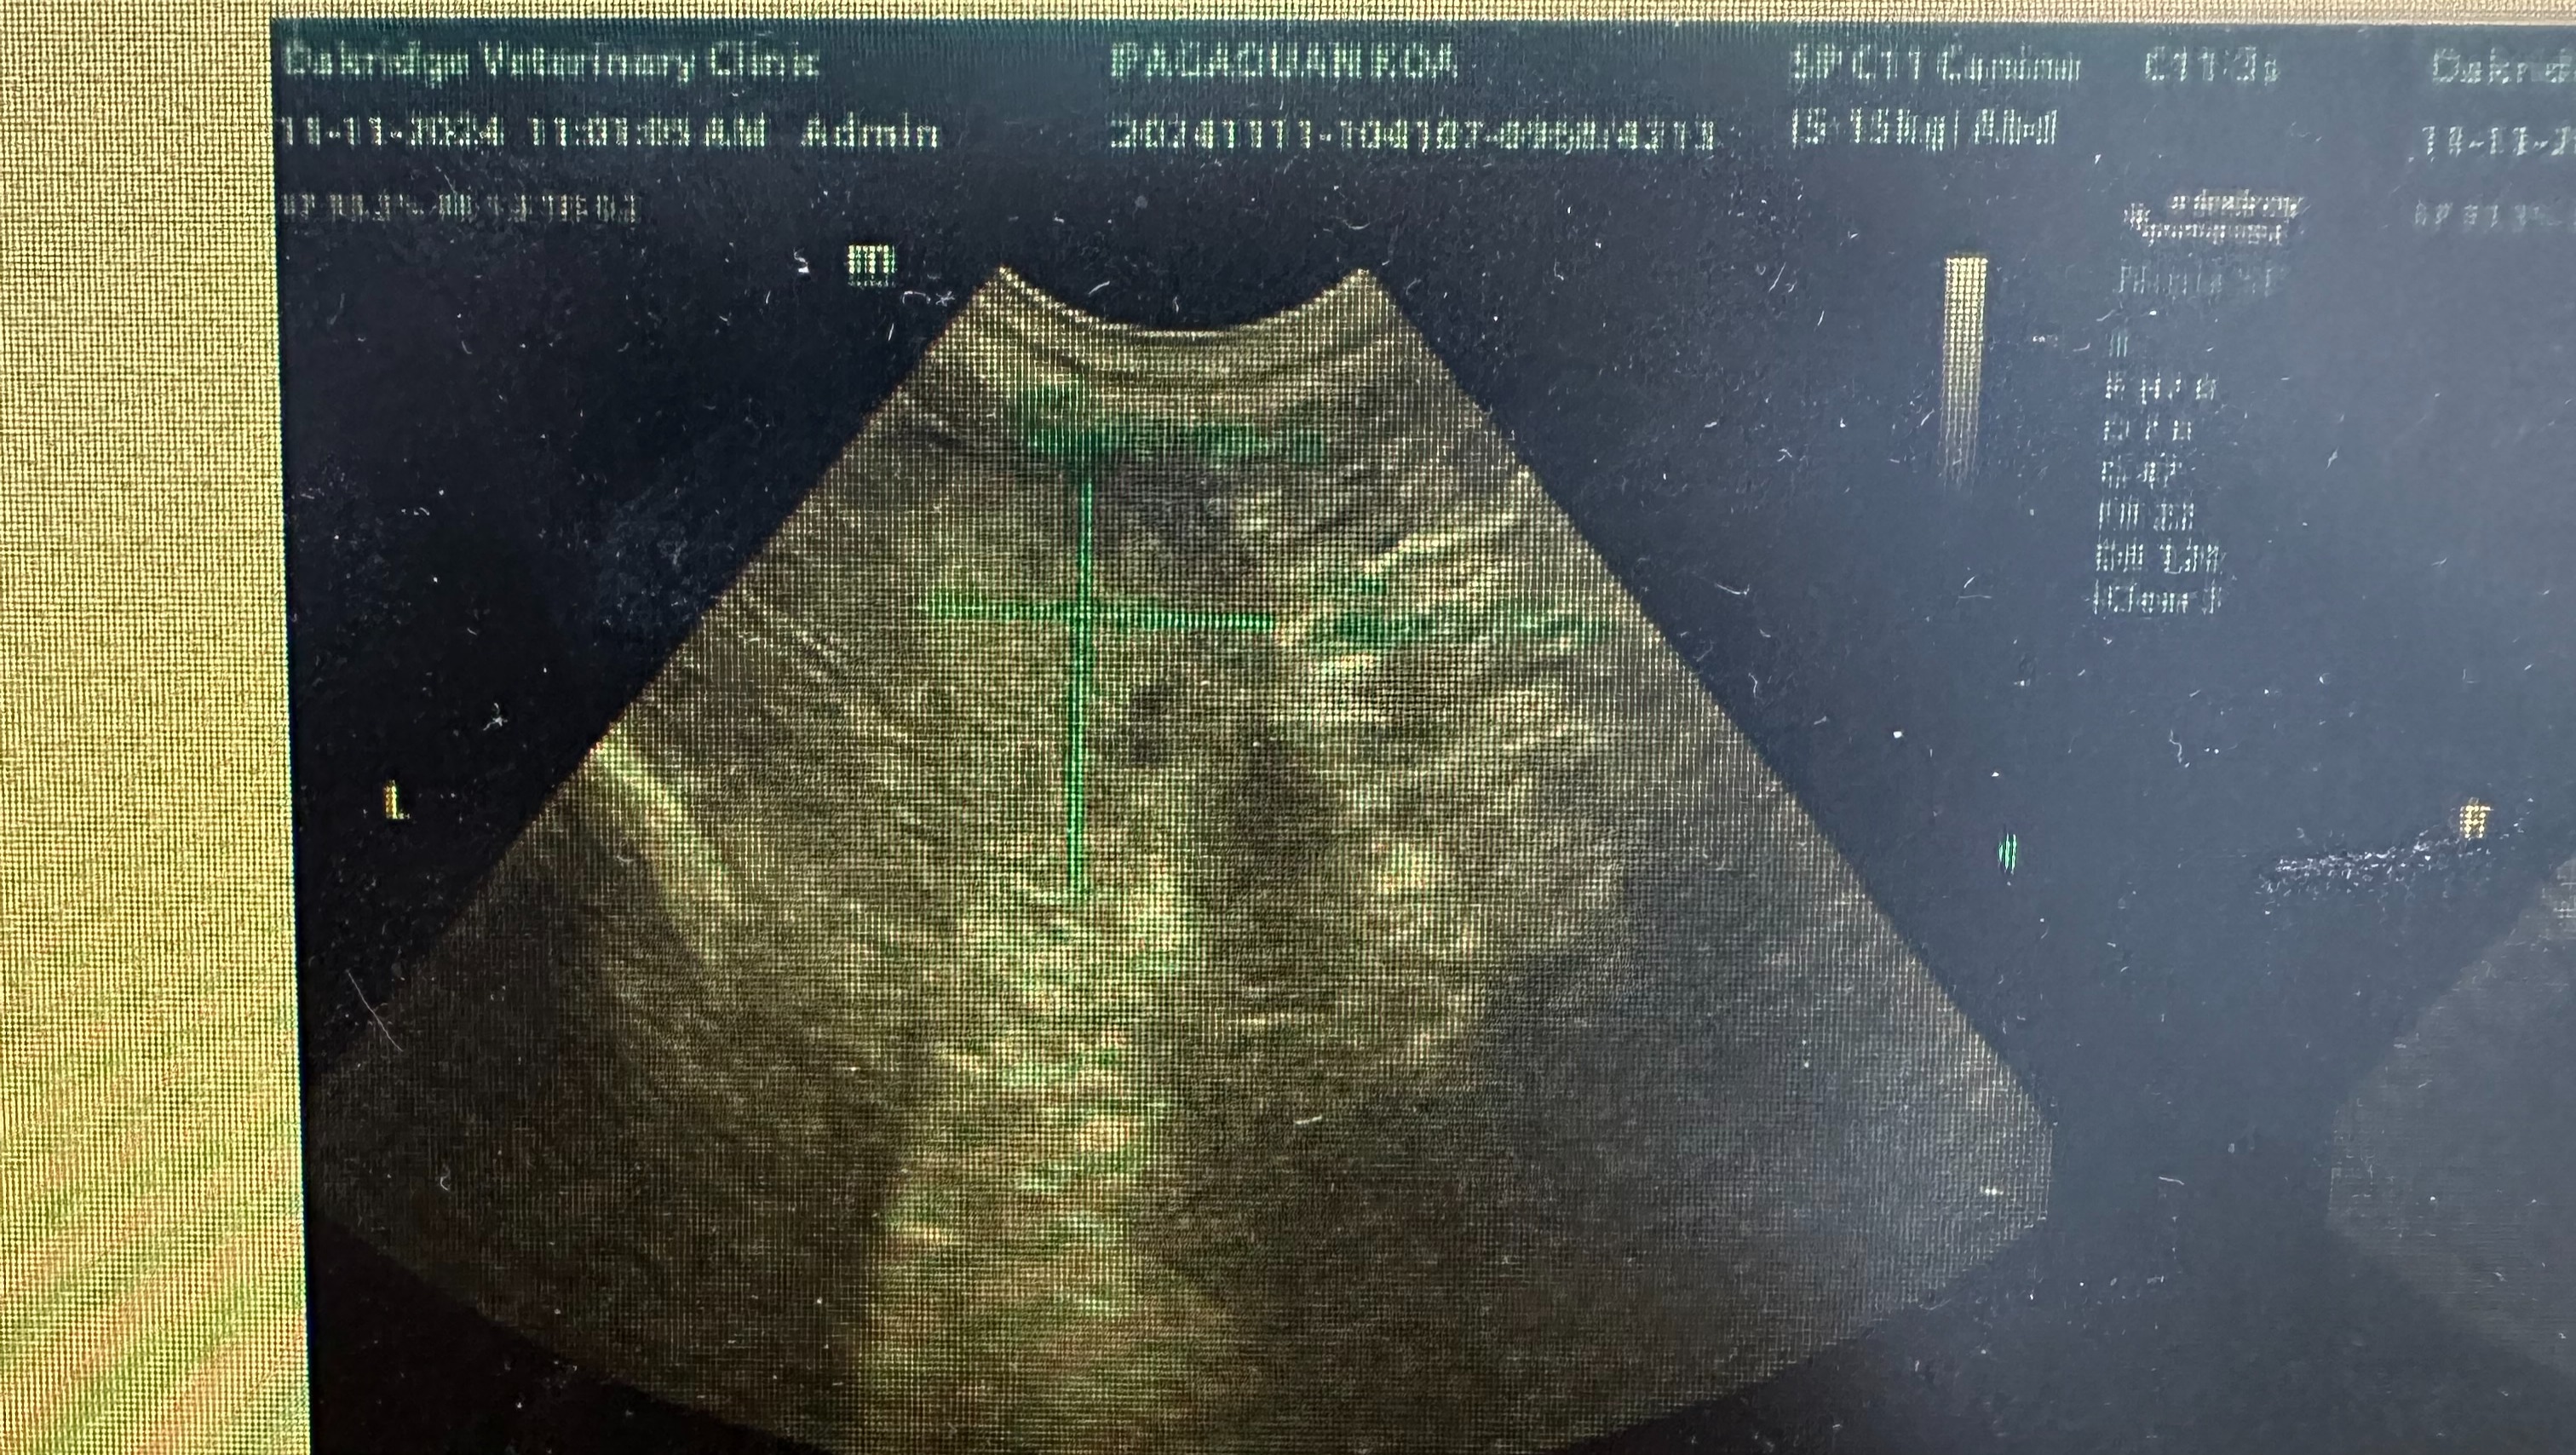

On November 11, 2024, Koa was brought into the clinic for a routine dental under anesthesia. Part of his senior screening included taking x-rays of his chest and abdomen. This is where we first saw the mass in his lungs. His dental was canceled and we performed an abdominal ultrasound which also found a small mass on his liver, and we were suspicious of the findings on his spleen. We were referred to a specialist for a CT scan to determine the next best steps. Our initial worry was that this was a cancer that had spread and made its way from the lungs to the liver and beyond.

Attached, you will find images of the lung mass from the x-rays circled in red. You will also find the image from the abdominal ultrasound confirming the presence of the mass on his liver marked by green lines indicating approximate measurements.